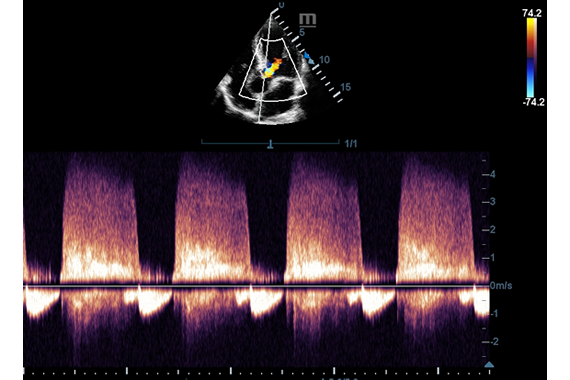

Клинические изображения

- Импульсно-волновой допплер (PW)

- Цветной допплер (Color Doppler)

- Импульсно-волновой допплер (PW)

- Цветной допплер (Color Doppler)

- P4-2 - Секторный фазированный датчик для кардиологических, транскраниальных и абдоминальных исследований

- P7-3 - Секторный фазированный педиатрический датчик для кардиологических, транскраниальных и абдоминальных исследований